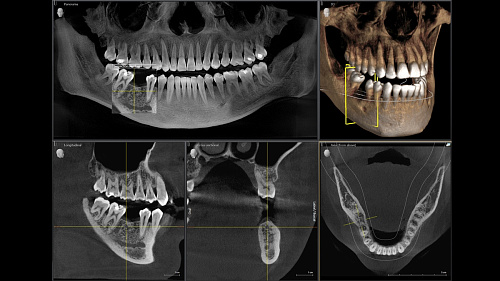

Диагностика последнего поколения, идеально решающая задачи рентгеновского обследования независимо от размеров клиники. Поля изображения зависят от определенной клинической картины, поэтому специалистам так удобно работать с ORTHOPHOS SL 3D. Данная установка делает объёмные картинки для одиночной реставрации в 3D качестве полностью всей челюсти такого размера, которого требуется.

Датчик DCS служит для выставления резкости снимков, причём его технологические особенности можно считать революционными для современного рынка стоматологического оборудования.

Планирование одиночной реставрации, эндодонтические исследования и пр. – для этого специалист может выбрать объёмные варианты 8 х 8 см или 11 х 10 см, также предлагается объём 5 х 5,5 см. Снимки в HD-качестве, стандартные настройки или выбор объёма обследования в зависимости от диагноза — всё это врач получает в отличном качестве, а для пациента излучение в районе исследования минимально.

Конструктивные особенности датчика DCS заключаются в превращении рентгеновского излучения в электрическую энергию. Обычная для таких случаев промежуточная стадия светового луча отсутствует. Другими словами, значительно снизив потери сигнала, производитель максимально улучшил чёткость.

С технологией SL можно за один сеанс получить огромное количество снимков. Те из них, где фокусировка наиболее чёткая, автоматически соединяются. В итоге одна процедура — снимки челюсти полностью в самом лучшем качестве. Даже нестандартные случаи не станут помехой в обследовании. К примеру, при ретинированных зубах уже после того, как снимок сделан, нужную область можно выделить подробнее, и в ещё одном рентгене необходимость отпадает.

Модернизированный сенсорный экран Easypad с понятным и удобным интерфейсом позволяет выставить наилучшие параметры контрастности и разрешения. Систематизация данных по диагностике становится значительно удобнее и проще с ПО обработки изображений SIDEXIS 4, ORTHOPHOS.

1. Двух-и трёхмерные снимки совмещаются в одной программе

2. В одном окне можно сравнивать разные 3D-результаты